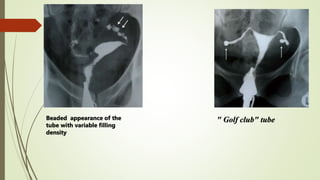

Beaded appearance of the

tube with variable filling

density

" Golf club" tube

Beaded appearance ofthe tube with variable filling density " Golf club" tube